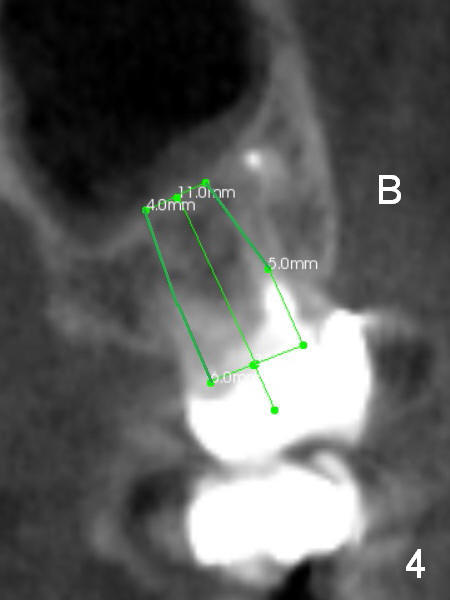

When the implant is placed in the middle of the socket (i.e., septum), it should be shorter (11 mm, Fig.4 coronal section) with sinus lift (bone graft), since the septum height is ~ 2.5 mm (Fig.5 (sagittal section) between arrowheads). The sinus floor dips in between the buccal and palatal roots. Initial osteotomy depth is 2 mm with a trephine bur (smallest). The burs have 2,4,6 mm marks.